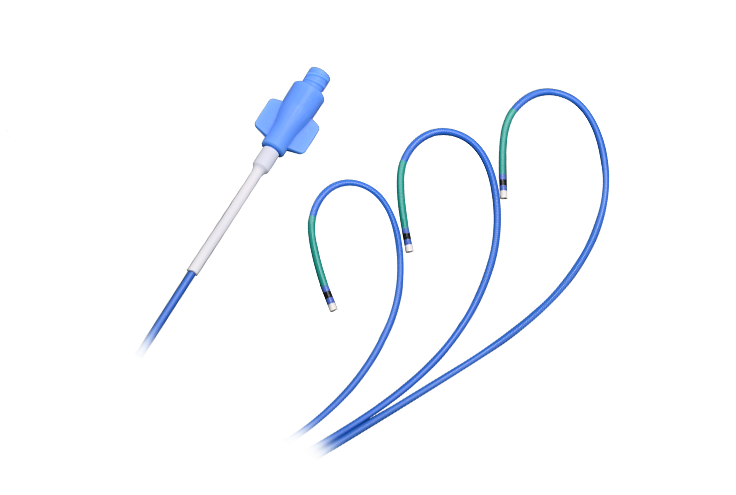

- Mikro katéter

- Endoskop

- Vodiaci katéter

- Angiografický katéter